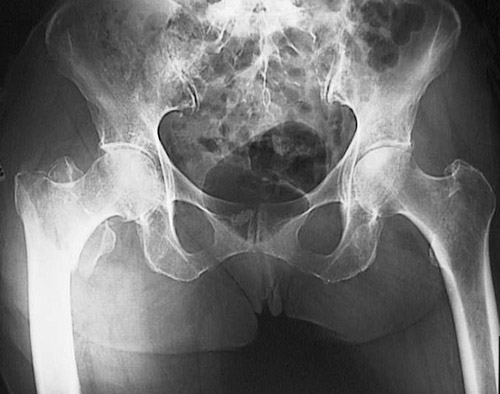

The radiograph of the pelvic region is shown above, with an intertrochanteric fracture located in the right femur of an elderly woman with osteoporosis. Below is the postoperative radiograph following surgical repair.